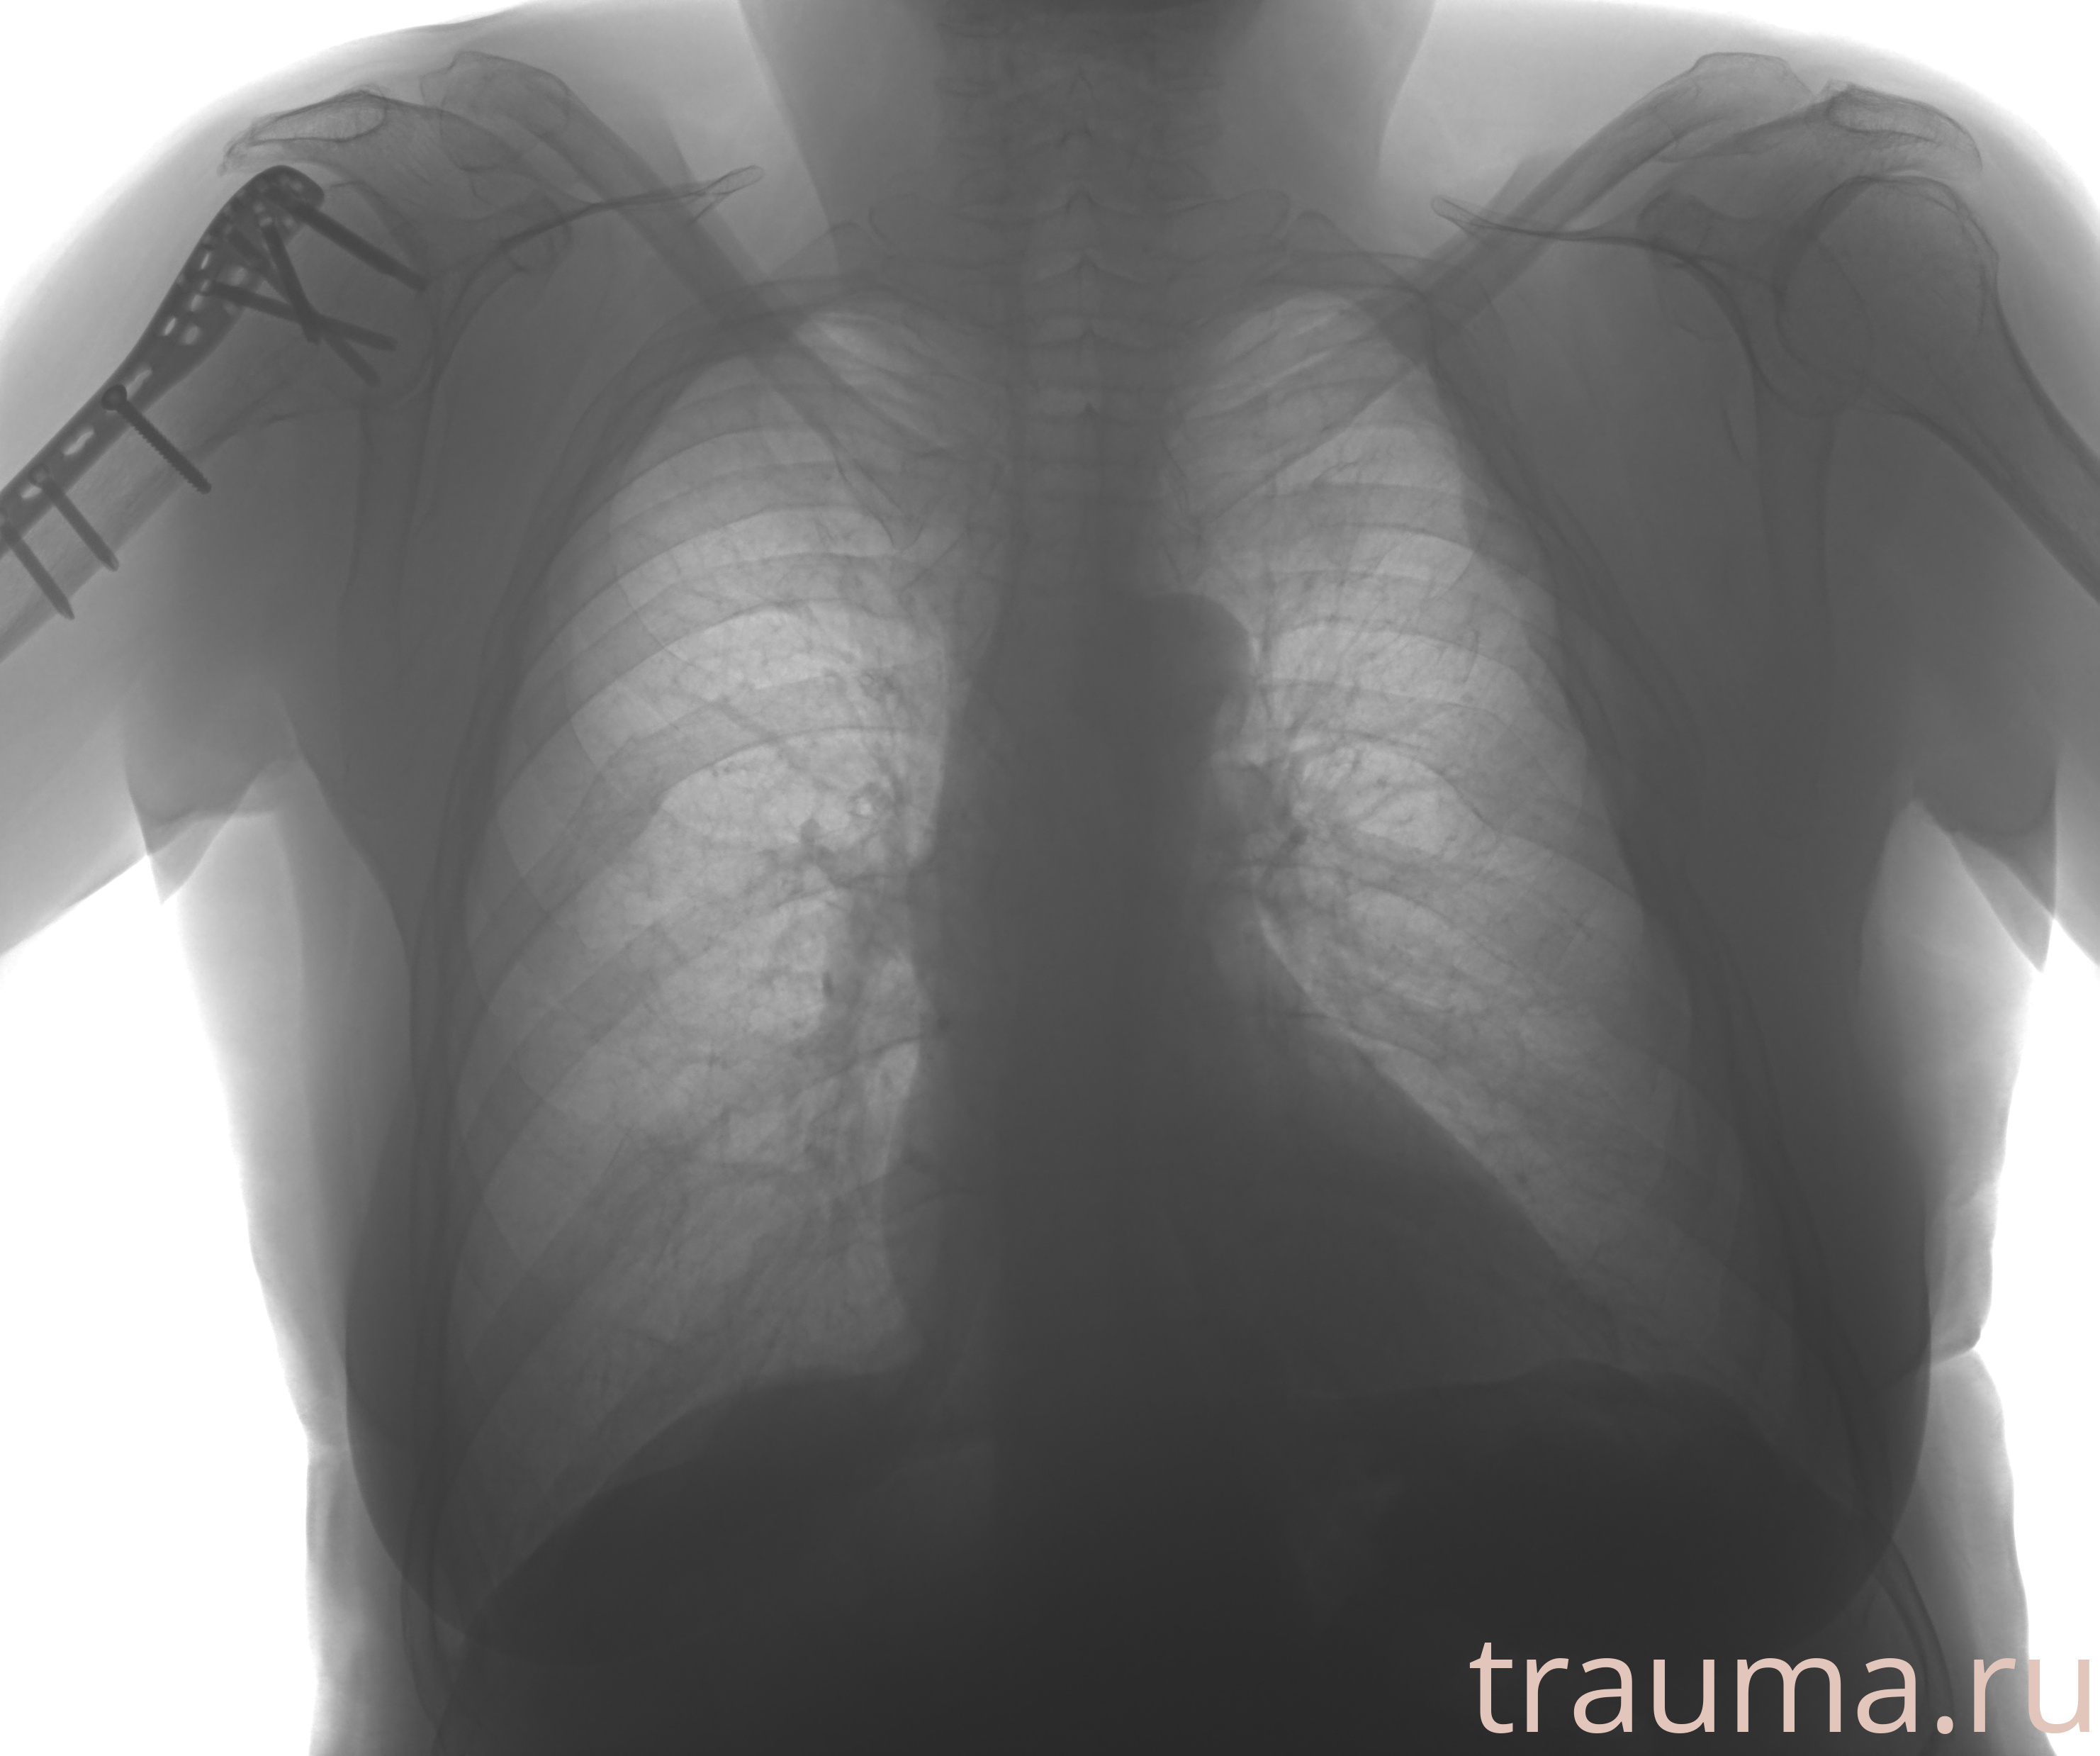

Рентгенограммы

Рентген на дому: по вашему адресу приезжает врач-рентгенолог, травматолог-ортопед с мобильным рентгеновским аппаратом, проводит диагностику травмы или заболевания, делает необходимые рентгенограммы, дает рекомендации по дальнейшему лечению. Получить качественные снимки в домашних условиях возможно благодаря уникальной методике, разработанной МосРентген Центром для института  Склифосовского

Яркость: 1   Контраст: 1   Инвертировать: 0 Увеличение: 1

Перетаскивайте мышь вверх/вниз для контраста, влево/право для яркости. Прокрутка колесом изменяет масштаб. Нажмите Сбросить для возврата к исходному изображению. При увеличении держите мышь в той области, которую хотите рассмотреть.